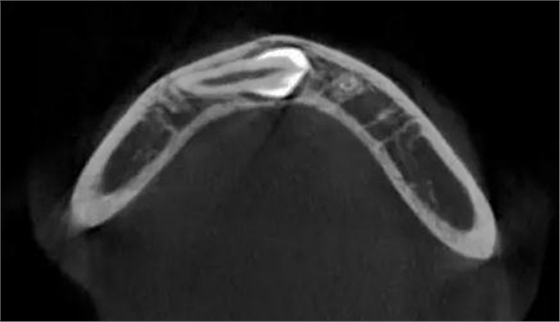

本案:患兒,女,14歲,因牙齒矯正來(lái)院,檢查見(jiàn)83滯留,43未見(jiàn)萌出,拍片發(fā)現(xiàn):43埋伏阻生于31、41、42根尖下方,按照正畸診療計(jì)劃,擬行43拔除術(shù)。

CBCT顯示